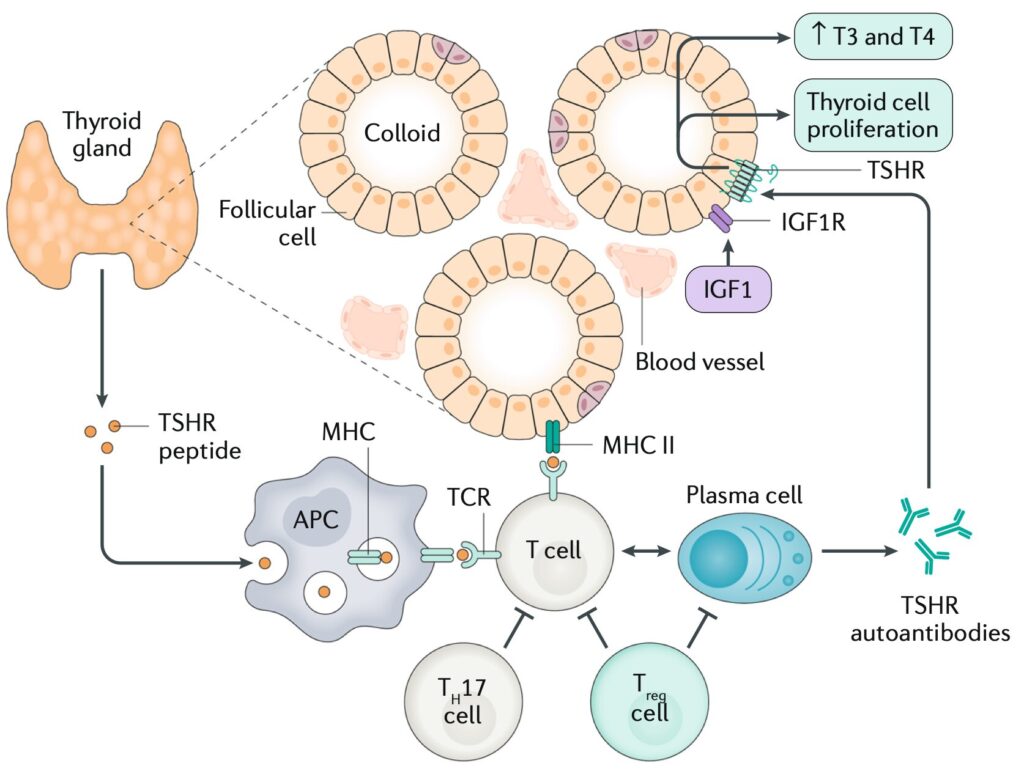

メカニズム

甲状腺細胞は甲状腺刺激ホルモン受容体(TSHR)自己抗体によって刺激され、甲状腺ホルモンであるトリヨードサイロニン(T3)とサイロキシン(T4)を分泌し、臨床症状を引き起こします。

自己抗体は、T細胞によって制御された局所のB細胞と形質細胞によって産生され、肝臓に由来するインスリン様成長因子1(IGF1)によって補助される。T細胞は抗原提示細胞(APC)上のTSHRペプチドによって活性化されます2)。